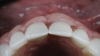

(19.) Four-month postoperative frontal and occlusal views revealing an ideal position of the tooth No. 9 margin in relation to its contralateral counterpart and an abundant amount of supracrestal soft tissue.

Figure 19

(20.) Four-month postoperative frontal and occlusal views revealing an ideal position of the tooth No. 9 margin in relation to its contralateral counterpart and an abundant amount of supracrestal soft tissue.

Figure 20

A patient presented for the restoration of an implant that had been placed at the site of tooth No. 9, which exhibited a residual soft-tissue deficiency and an undulating facial soft-tissue morphology (Figure 11). The objective of the treatment was to change the appearance and thickness of the facial soft tissue prior to crown placement to optimize the esthetics and prevent future soft-tissue dehiscence. After flap reflection (Figure 12), a graft was acquired from the patient's tuberosity to augment the supracrestal soft tissue (Figure 13). A volume-stable collagen matrix was then placed to further increase the thickness of the soft tissue adjacent to the implant body (Figure 14), and the flap was sutured closed (Figure 15). Following a 3-month healing period, a positive change in the soft tissue's morphology was apparent; however, its volume remained deficient when compared with that of tooth No. 8 (Figure 16). When the screw-retained crown was delivered, a second graft was acquired from the tuberosity and placed to further increase the volume of the supracrestal soft tissue (Figure 17 and Figure 18). A postoperative healing period of 4 months resulted in an ideal position of the margin of tooth No. 9 with regard to its contralateral counterpart as well as more natural looking soft-tissue morphology and excellent supracrestal soft-tissue thickness (Figure 19 and Figure 20). Eight months postoperatively, the position of the gingival margin and the thickness of the soft tissue had been maintained (Figure 21 and Figure 22).